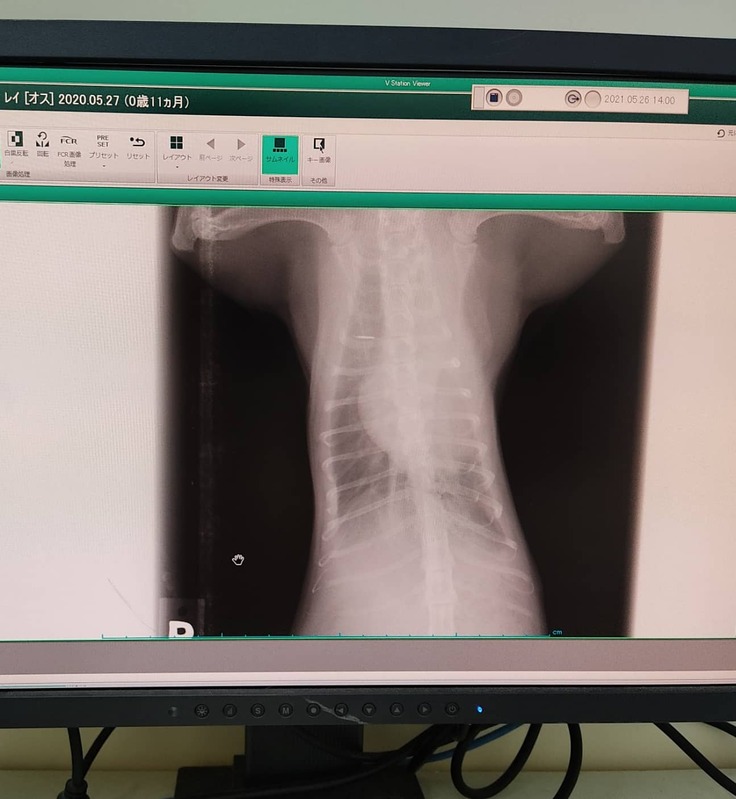

さっそくレントゲンと血液検査をしたところ

「肺が真っ白で肺炎ですね」と診断され、以前に効いた同じ抗生物質のお薬をいただき解熱剤の注射をしてもらって帰宅しました。

39.9℃の熱があるなかCT検査をした結果、

レントゲンで肺が真っ白に見えていたものは実は胸のリンパ節が腫れていたものであり、

肺炎ではないという診断がくだされました。

ほかに、胸水と腹水が少したまっているのが映っていました。

それにより、疑われる病気は第1にFIP(猫伝染性腹膜炎)で可能性が高く、

第2にリンパ節のガンと言われました